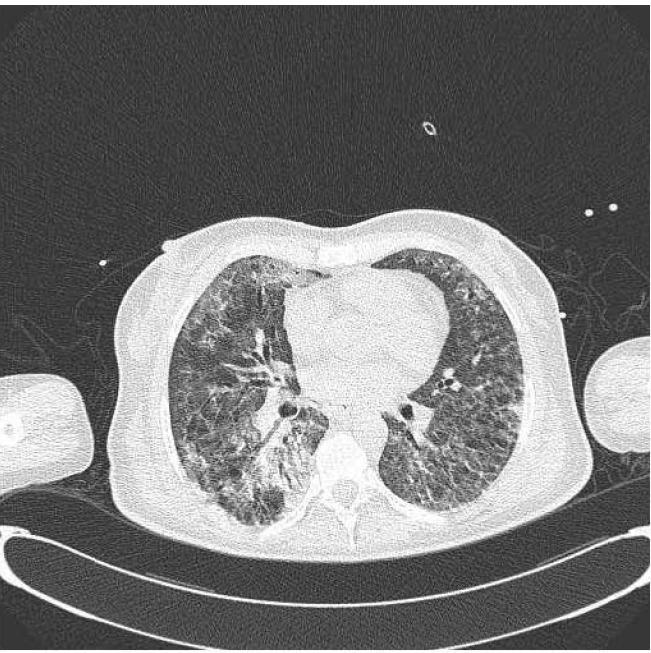

Lobar fiberoptic lung lavage is a well-known procedure used in primary pulmonary alveolar proteinosis (PAP); the use of this procedure has increased in the recent years. This procedure has also been used in other pulmonary diseases such as desquamative interstitial pneumonia with good results. We describe a case of extremely severe respiratory failure due to concurrence of PAP and Influenza A H1N1 virus pneumonia which resolved with the help of this procedure. The patient, a 41-year-old woman, needed less mechanical ventilation after undergoing lobar fiberoptic bronchoscopic lavage. Moreover, a rapid and progressive improvement in the computed tomography of the lungs was observed. Flexibile fiberoptic bronchoscopic lobar lavage is a simple, safe procedure used not only in milder disease, but also in particular severe cases in which the physiological derangement of whole lung lavage would not be tolerated by patient or when extra-corporeal membrane oxygenation is not available.

肺叶纤维支气管镜灌洗是用于原发性肺泡蛋白沉积症(PAP)的一种众所周知的操作;近年来该操作的使用有所增加。此操作也已用于其他肺部疾病,如脱屑性间质性肺炎,效果良好。我们描述了一例因PAP与甲型H1N1流感病毒肺炎并发导致的极其严重的呼吸衰竭病例,该病例通过此操作得以解决。患者为一名41岁女性,在接受肺叶纤维支气管镜灌洗后所需机械通气减少。此外,肺部计算机断层扫描显示有快速且逐步的改善。可弯曲纤维支气管镜肺叶灌洗是一种简单、安全的操作,不仅用于病情较轻的疾病,也用于病情特别严重的病例,在这些病例中,全肺灌洗的生理紊乱患者无法耐受,或者无法进行体外膜肺氧合。